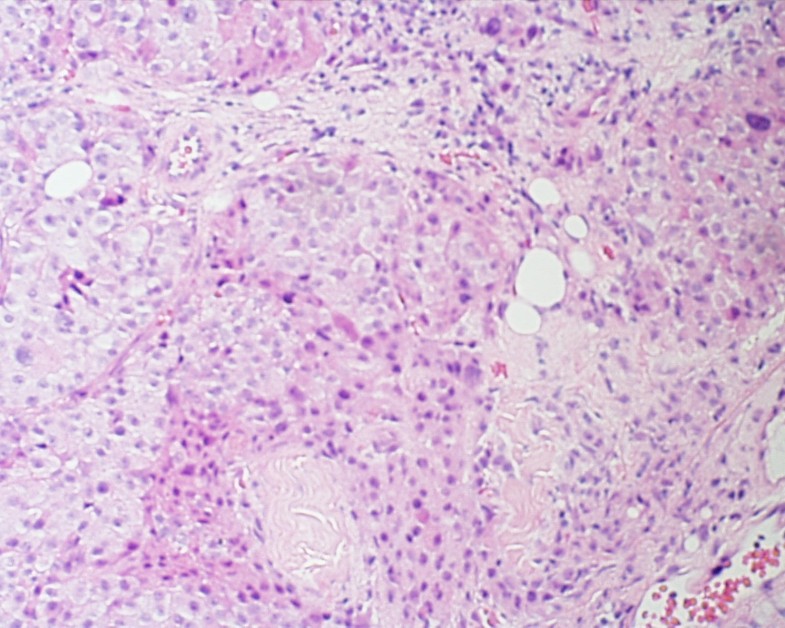

Surgery to remove the thyroid gland is the most common treatment. Hurthle cell neoplasms originate in thyroid follicles from follicular cells (hence they were initially grouped with follicular thyroid tumors) and are characterized by the presence of hurthle cells, which are eosinophilic oxyphilic cells with round to oval nuclei with prominent nucleoli, and small densely packed mitochondria giving a granular appearance to the otherwise.

Although rare, it is quite aggressive in nature and requires surgical removal of the gland as the first line of treatment. The oncocytic follicular cells of the thyroid continue to carry the name “hürthle cells”, even though the cells that karl hürthle initially identified in 1894 ultimately proved to be the parafollicular c cells (hürthle 1894). Hurthle cell neoplasms originate in thyroid follicles from follicular cells (hence they were initially grouped with follicular thyroid tumors) and are characterized by the presence of hurthle cells, which are eosinophilic oxyphilic cells with round to oval nuclei with prominent nucleoli, and small densely packed mitochondria giving a granular appearance to the otherwise.

1 they are large, polygonal cells with marked eosinophilic, granular cytoplasm reflective of overly. Invasive hurthle cell carcinoma of the thyroid: Removal of the entire thyroid).